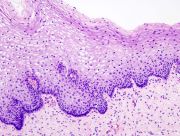

| 2021年7月26日 (一) 18:21 | Cervical intraepithelial neoplasia (1) normal squamous epithelium.jpg (文件) |  |

97 KB | 77921020 | Uploaded with SimpleBatchUpload | 1 |